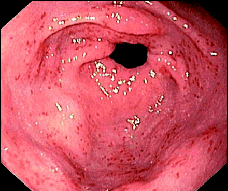

El diagnóstico diferencial es con el eritema cofluente al píloro (comb-like erythema) (Figura 3), la gastritis hemorrágica y la gastropatía portal hipertensiva. La diferenciación entre el GAVE (Figura 4) y la gastropatía portal hipertensiva es de suma importancia ya que el sangrado de esta última responde al tratamiento con beta bloqueadores. No es infrecuente que al paciente se le hayan practicado varias gastroscopias antes de que el diagnóstico de GAVE sea considerado (Figura 5).

Figura 3. Imagen endosc+opica de un caso de eritema cofluente al píloro (comb-like erythema)